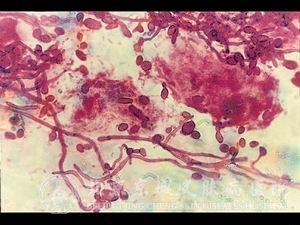

北京京城皮肤医院指出,内脏念珠菌病包括念珠菌性肠炎,念珠菌性支气管炎,念珠菌性泌尿道炎,还有念珠菌还可以引起心内膜炎、脑膜炎、食道炎、败血症等,亦可侵犯脾、肝等其它内脏。